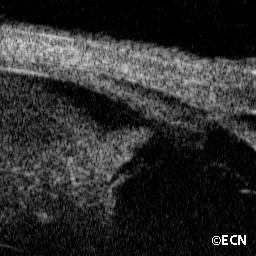

Infiltrative choroidopathy

Infiltrative choroidopathy (10 MHz ultrasound) - Note the choroidal thickening (arrow), also widening of the optic nerve shadow and papilledema.